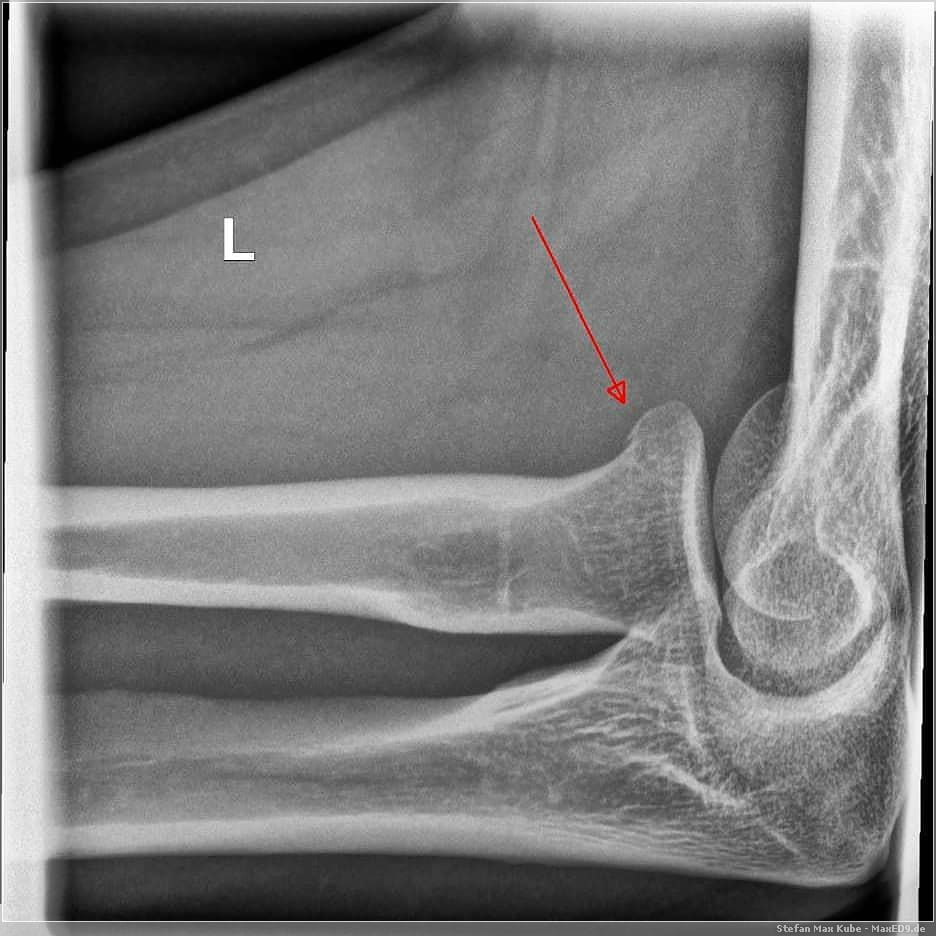

Ein jähes Ende fanden meine sportlichen Aktivitäten am 18. Okotber als ich auf dem Weg zur Arbeit mit dem Hinterrad auf feuchtem Laub wegrutschte und nach links stürzte. Ich konnte sofort wieder aufstehen und spürte zunächst nur leichte Schmerzen. Die Sturzerkennung meines Garmin Edge 820[4] funktionierte hier zuverlässig, ich unterbrach den Notruf jedoch und setzte meine Fahrt vorsichtig fort.

Der linke Arm tat dann schon etwas mehr weh, richtig aufstützen war nicht möglich und ich dachte, dass hier nur ein Prellung vorliegt und sich das schon geben wird.

Dem war nicht so und am Ende kam ich mit einem Gipsarm aus dem Krankenhaus, da ich eine Radiusköpfchenfraktur hatte. Das war es dann mit Sport für die nächste Zeit.

Nach 2 Wochen kam der Castverband weg und ich bekam eine Orthese, um langsam wieder Bewegung in den Arm zu bekommen. Nach 4 Wochen durfte ich dann wieder den Arm frei benutzen. Laufen war dann schon ok, aber noch kein Radfahren, das durfte ich bis zum Jahresende leider nicht mehr.